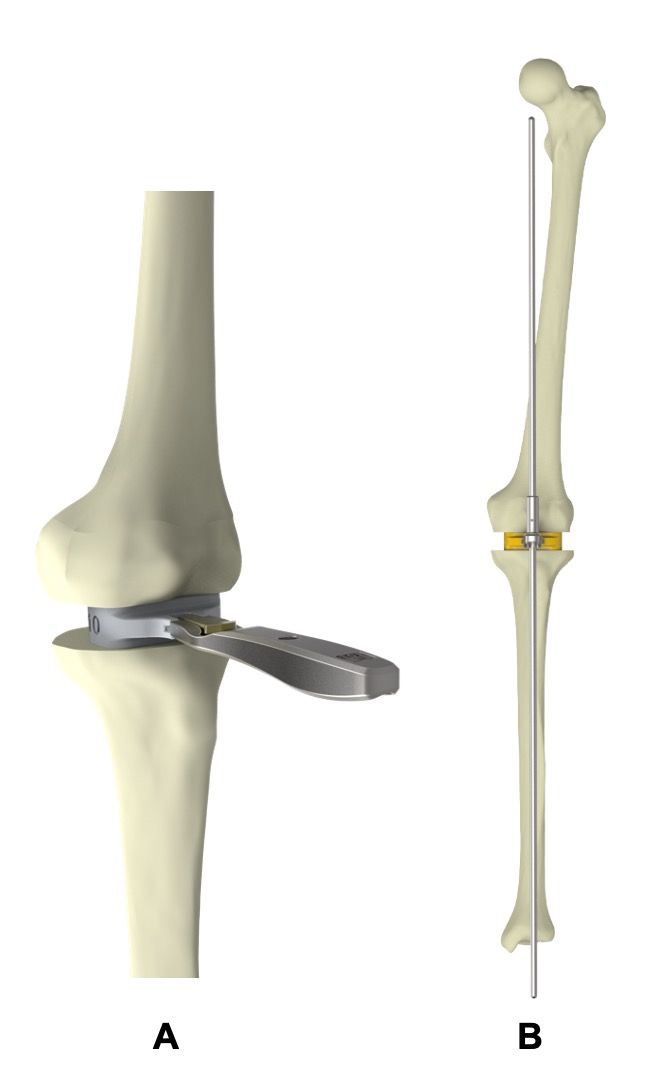

After creating the intramedullary entry point, the intramedullary rod is inserted into the femoral canal up to the score line, using the impactor handle. The measured femoral valgus (0°–10°) is adjusted through simple traction, using the dial. The distal femoral cutting guide is then slid onto the template, right down to femur (Figure 3).

Extramedullary verification is possible. The cutting guide is then stabilized against femur using two long pins. It can be detached from the main body of the tool by pressing the gold release button, and the intramedullary rod can be withdrawn (Figure 4).